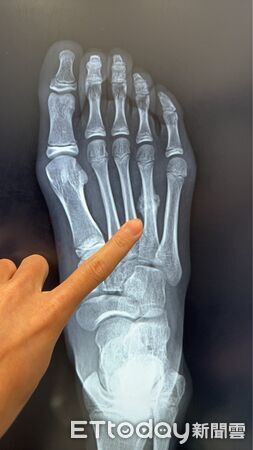

▲11歲女學童右腳掌「蹠骨應力性骨折」,影像顯示已有癒合跡象。

暑假與寒假是孩子最期待的運動時光,但密集的田徑、球類或游泳活動,也可能埋下健康隱憂,一名11歲女學童因暑假連續參加田徑與球類訓練,右腳掌疼痛兩周未緩,檢查後確診為「蹠骨應力性骨折」,且已出現癒合跡象,提醒家長與師長切勿掉以輕心。

陳建宏醫師表示,蹠骨位於腳掌前端,是行走、跑跳時主要承受壓力的部位。當骨頭長期反覆承受過大應力,缺乏足夠休息與修復時間,便可能出現顯微骨折,即「應力性骨折」。與一般一次性外力骨折不同,應力性骨折多為長期累積造成,初期症狀不明顯,常被誤認為拉傷或扭傷。此次案例也打破了「應力性骨折只發生於成人或專業運動員」的刻板印象。